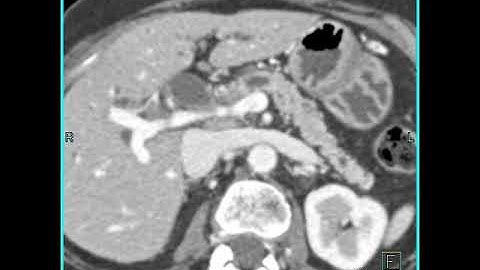

Abdomen: Pancreas: Pancreatic cancer : 3D mapping using volume rendering and MIP: Axial